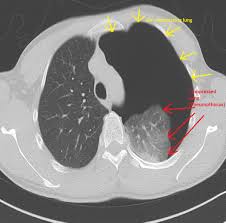

Scielo Brasil Pneumothorax As A Late Complication Of Covid 19 Pneumothorax As A Late Complication Of Covid 19 from minio.scielo.br In tension pneumothorax, patients are distressed with rapid laboured respirations, cyanosis, profuse diaphoresis, and tachycardia. The definition of a pneumothorax is an accumulation of air outside the lungs, but inside the chest wall. Tension pneumothorax most commonly occurs in people with penetrating chest injuries. In a healthy body, the lungs are touching the walls of the chest. Patients with a pneumothorax typically report dyspnoea and chest pain. A pneumothorax occurs when air leaks into the space between the lung and chest wall (called the pleural space). A small pneumothorax may cause few or no symptoms. Pneumothorax occurs when air enters the space around your lungs (the pleural space).

Other signals that the problem may be a collapsed lung are: Normally, the outer surface of the lung sits next to the inner surface of the chest wall. The lung and the chest wall are covered by thin membranes called pleura. It occurs when air accumulates between the parietal and visceral pleura inside the chest. Pneumothoraces can be even further classified as simple, tension, or open. A pneumothorax is an abnormal collection of air in the pleural space between the lung and the chest wall. Pneumothorax is defined as the presence of air or gas in the pleural cavity (ie, the potential space between the visceral and parietal pleura of the lung), which can impair oxygenation and/or. A pneumothorax occurs when air leaks into the space between your lung and chest wall. The pressure causes the lung to give way, at least partly. Pneumothorax is classified as spontaneous or traumatic. Hemothorax occurs when there is blood in that. This air pushes on the lung, which makes it collapse. The air accumulation can apply pressure on the lung and make it collapse.

Pneumothorax Physiopedia from www.physio-pedia.com Women with catamenial pneumothorax have recurrent episodes of pneumothorax that occur within 72 hours before or after the start of menstruation. This air pushes on the outside of your lung and makes it collapse. A hole might grow in the surface of the lung. Pneumothorax (sometimes called collapsed lung) is a health problem where air or gas is in the pleural space (the space between the lung and the pleura). The pressure causes the lung to give way, at least partly. Human beings have a complete and strong mediastinum so that pneumothorax is generally unilateral and thus not a serious problem. A special form of the traumatic pneumothorax is the iatrogenic pneumothorax occurring as a result of diagnostic and/or therapeutic interventions. A pneumothorax is a collapsed lung.

While secondary pneumothorax is caused by an underlying pulmonary disease, the spontaneous type occurs in healthy individuals without obvious cause. When there is no apparent cause, the condition is known as spontaneous pneumothorax. Other signals that the problem may be a collapsed lung are: Pneumothorax is classified as spontaneous or traumatic. Normally, the outer surface of the lung sits next to the inner surface of the chest wall. There are several variations of pneumothorax. It occurs when air accumulates between the parietal and visceral pleura inside the chest. A tension pneumothorax can cause complete collapse of the nearby lung and can push the heart and major blood vessels to the other side of the chest. A collapsed lung requires immediate medical care. Patients with a pneumothorax typically report dyspnoea and chest pain. This air pushes on the outside of your lung and makes it collapse. The lung and the chest wall are covered by thin membranes called pleura. Also known as pneumothorax, collapsed lung is a rare condition that may cause chest pain and make it hard to breathe.

Patients with a pneumothorax typically report dyspnoea and chest pain. Pneumothoraces can be even further classified as simple, tension, or open. Pneumothorax is defined as the presence of air or gas in the pleural cavity (ie, the potential space between the visceral and parietal pleura of the lung), which can impair oxygenation and/or. In a healthy body, the lungs are touching the walls of the chest. The definition of a pneumothorax is an accumulation of air outside the lungs, but inside the chest wall. It is reasonably common and has many different causes. A pneumothorax is a collection of air outside the lung but within the pleural cavity. A pneumothorax can be a complete lung collapse or a collapse of only a portion of the lung. A pneumothorax occurs when air leaks into the space between the lung and chest wall (called the pleural space). This air pushes on the lung, which makes it collapse. Also known as pneumothorax, collapsed lung is a rare condition that may cause chest pain and make it hard to breathe. A large pneumothorax can squash the lung and cause it to collapse. This is termed spontaneous pneumothorax.